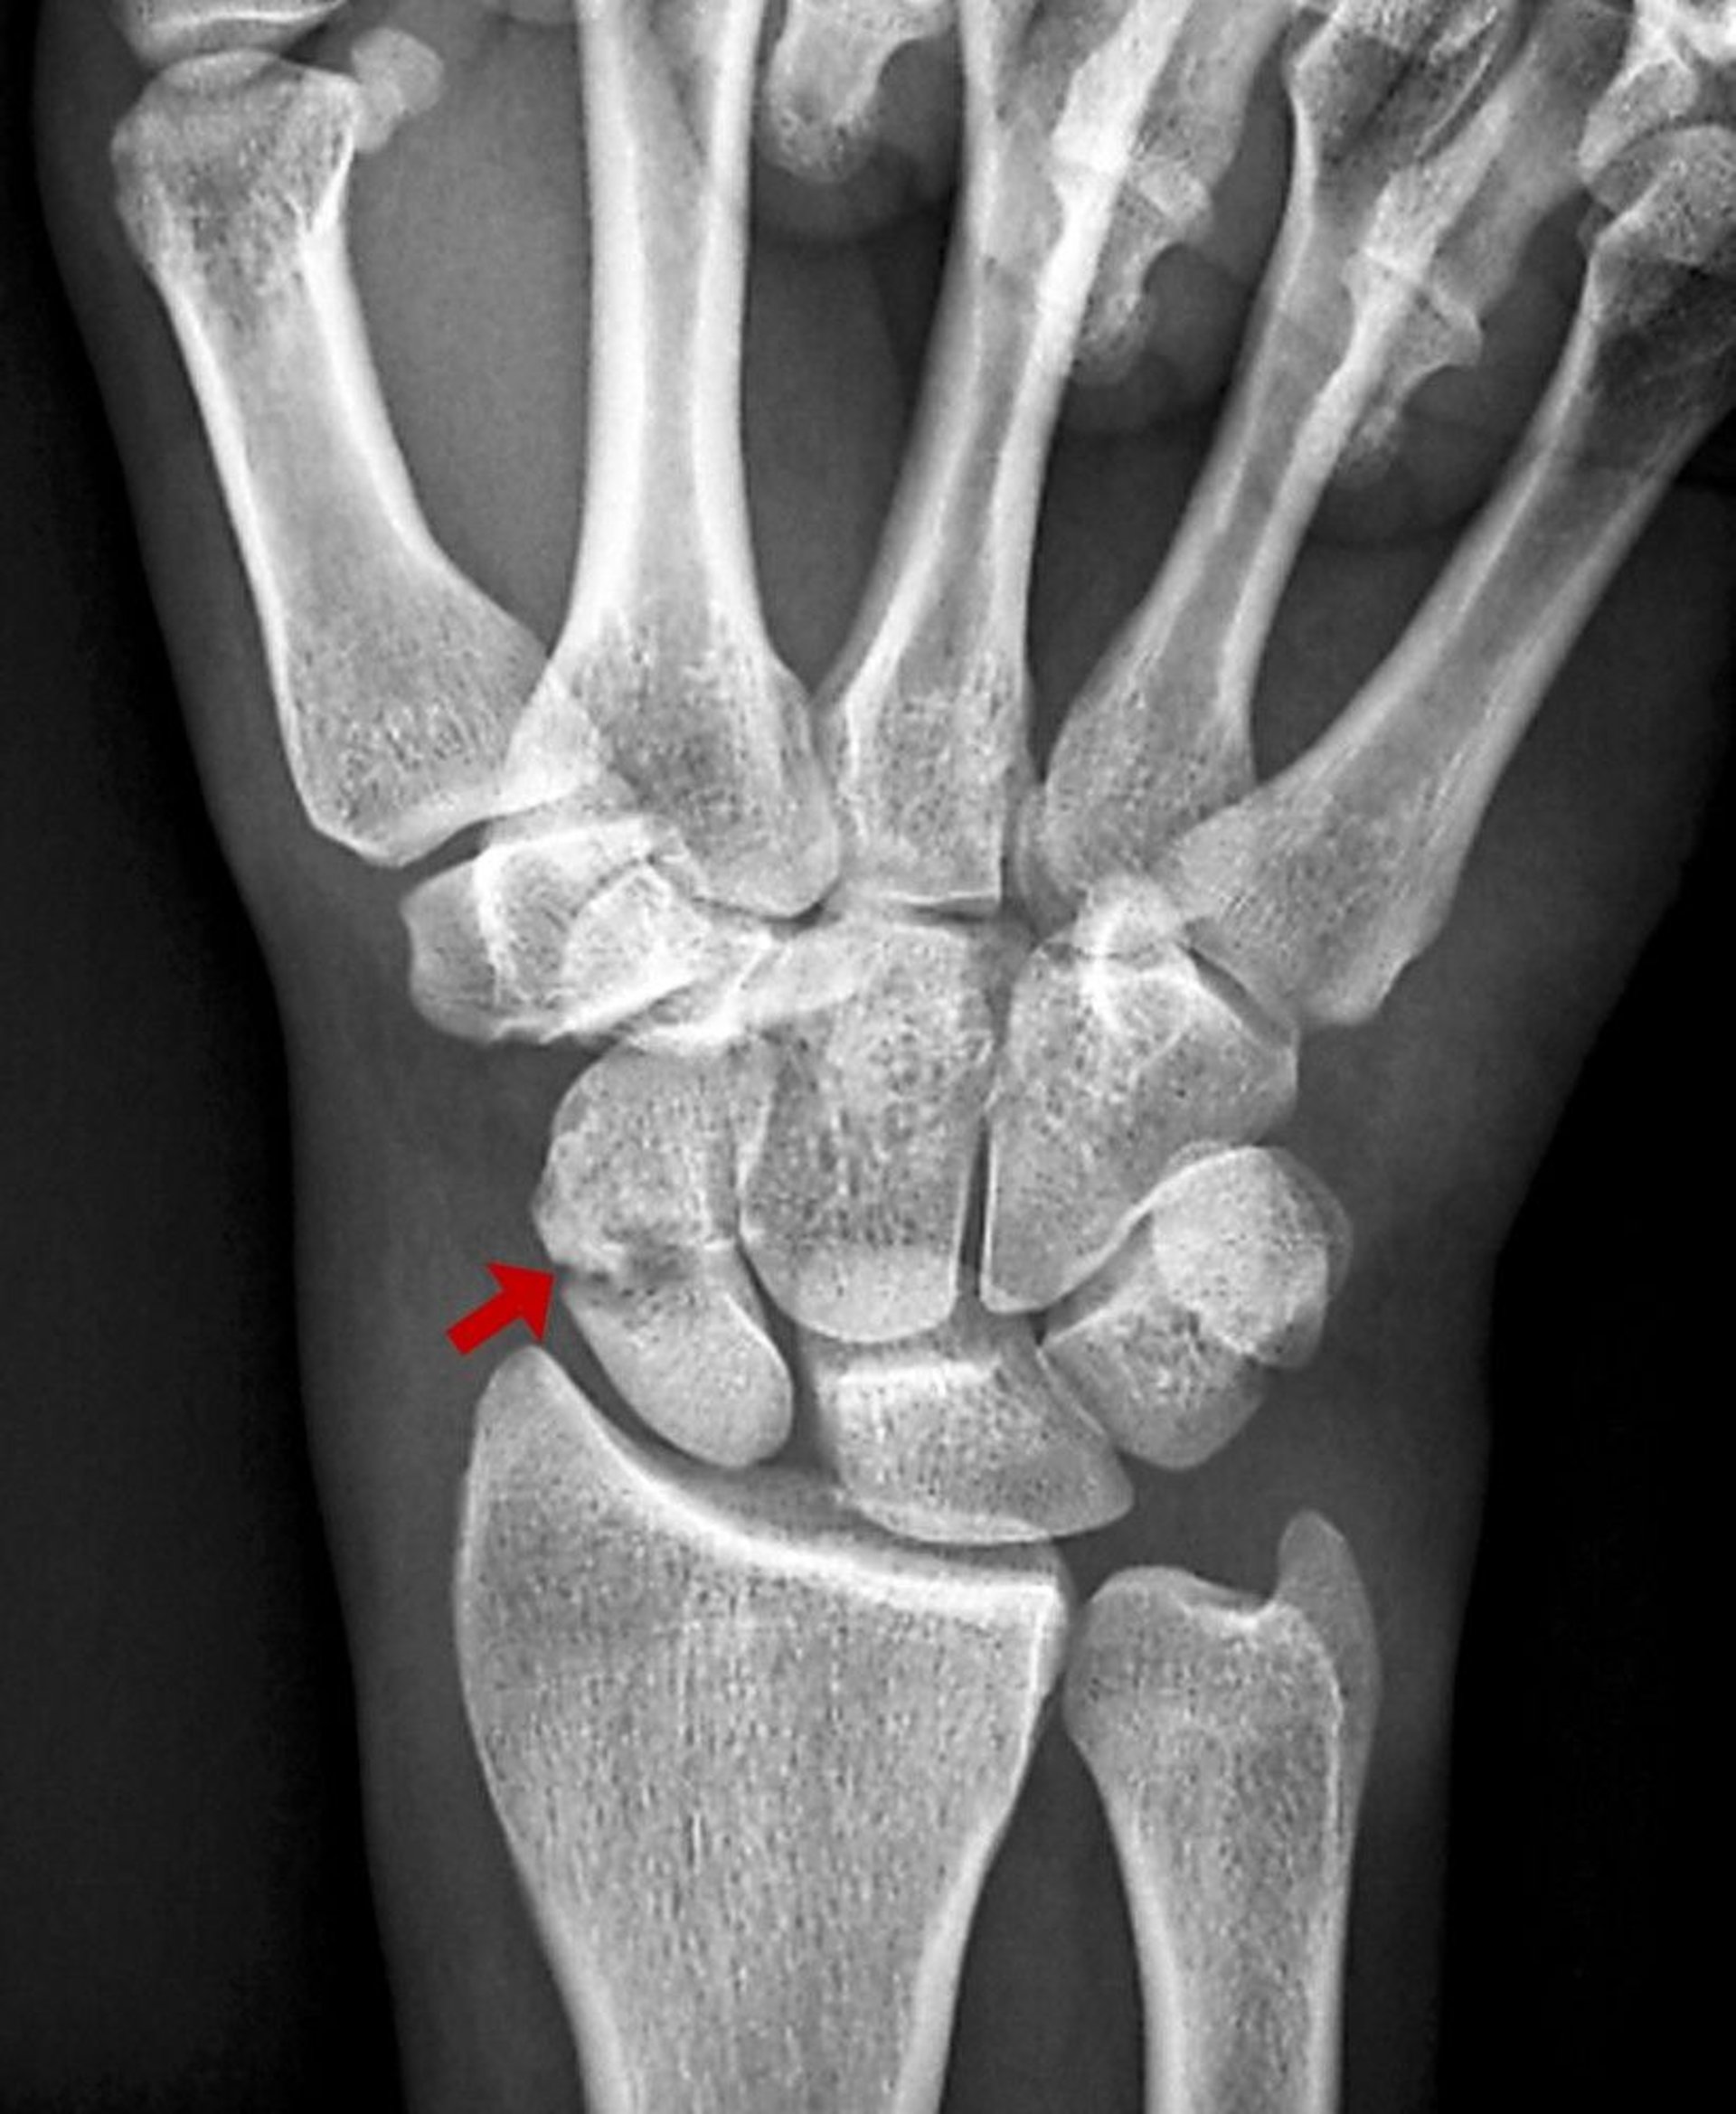

Scaphoid Fracture

This scaphoid fracture is visible as a lucency on radiograph.